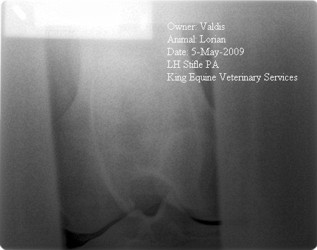

Posted on Thursday, May 14, 2009 - 12:51 pm: Dear Dr. O.,Thank you for your quick response. I have asked myself how could it get this bad this fast. As background information though, my horse has had warm up lameness off and on, just not enough to be locatable. He has had troubles with certain dressage movements which has given me "this feeling" that something is wrong for a long time and I thought about getting him x-rayed just for that, but again, nobody was sure which joint is causing it. I think now it finally manifested itself in a real noticeable lameness. Another indicator for pain is his change in behavior. He started turning unpredictably aggressive over the winter. He is on bute now and seems much happier again, but that’s not a long term option as he already had ulcers in the past. Surgery is not really an option because he can’t be stall rested as he jumps and paces in his stall the second the barn door opens. Only option seems Depo injections or IRAP, but if none of these will get him sound again one really has to question it. I attached some x-rays, but with this low resolution I don’t know how much you will see. The vets and surgeon looked at it on a high res screen. What do you think?

Posted on Monday, May 18, 2009 - 11:24 am: Delia, in the first image I do think the opacity that spans the front of the joint just cranial to the tibial tuberosity could represent a mineralized cranial border of the meniscus but I would want a radiologist to review this as it is not a lesion I have seen before and I cannot find an example of it in any of the references I have. It also has an irregular of "fibrillated" appearance. We also see several osteophytes (bone spurs) and the one on the proximal tibia has been associated with chronic meniscus injuries.Most of these cases do have a poor prognosis without surgery and even with surgery to debride torn tissue and possible suture any partially torn ligaments the prognosis is improved but still guarded. DrO |

Posted on Monday, May 18, 2009 - 8:52 pm: Thank you Dr.O,The radiologist and the surgeon at our university clinic reviewed these x-rays and were the ones who told my local vet that the lateral meniscus is entirely calcified. We all think that my horse must have had an injury in his early years. I have owned this horse for 3.5 years and he certainly didn't incur this injury during that time. He came to me in very poor condition from some backyard breeder who had neglected him, hence I didn’t get a PPE done and never had him x-rayed. By chronic meniscus injury you mean an injury that never healed up properly or an injury that keeps recurring? Looking at these x-rays – would you expect to see torn ligaments? Only way to find out is surgery, correct? Could he even have been sound for all this time with a torn ligament? That “fibrillated” mass in front of the joint – if it’s not some sort of calcification, what else could it be? If surgery is not really an option for previously described reasons what potential treatment would you chose and why? Thank you again for looking at this and sharing your insights |

Posted on Tuesday, May 19, 2009 - 9:37 am: Delia,You would not expect to see torn ligaments radiographically and yes surgery required for a better diagnosis. Because everyone's goals, resources, and willingness to assume risk are different, I cannot make useful specific recommendations for you. Our recommendations for treating arthritis, including IRAP, are put forward in the article on Overview of Arthritis and details of most of the treatments are fleshed out in detail in their own articles which are linked to from the arthritis article. Whatever your decision is must be based on the notion that the prognosis for return to soundness is poor based on the radiographic findings. I think your history suggests a slightly better prognosis however. Though I have not seen such an appearance I think that fibrillated mass in the cranial extent of the calcified meniscus. DrO |